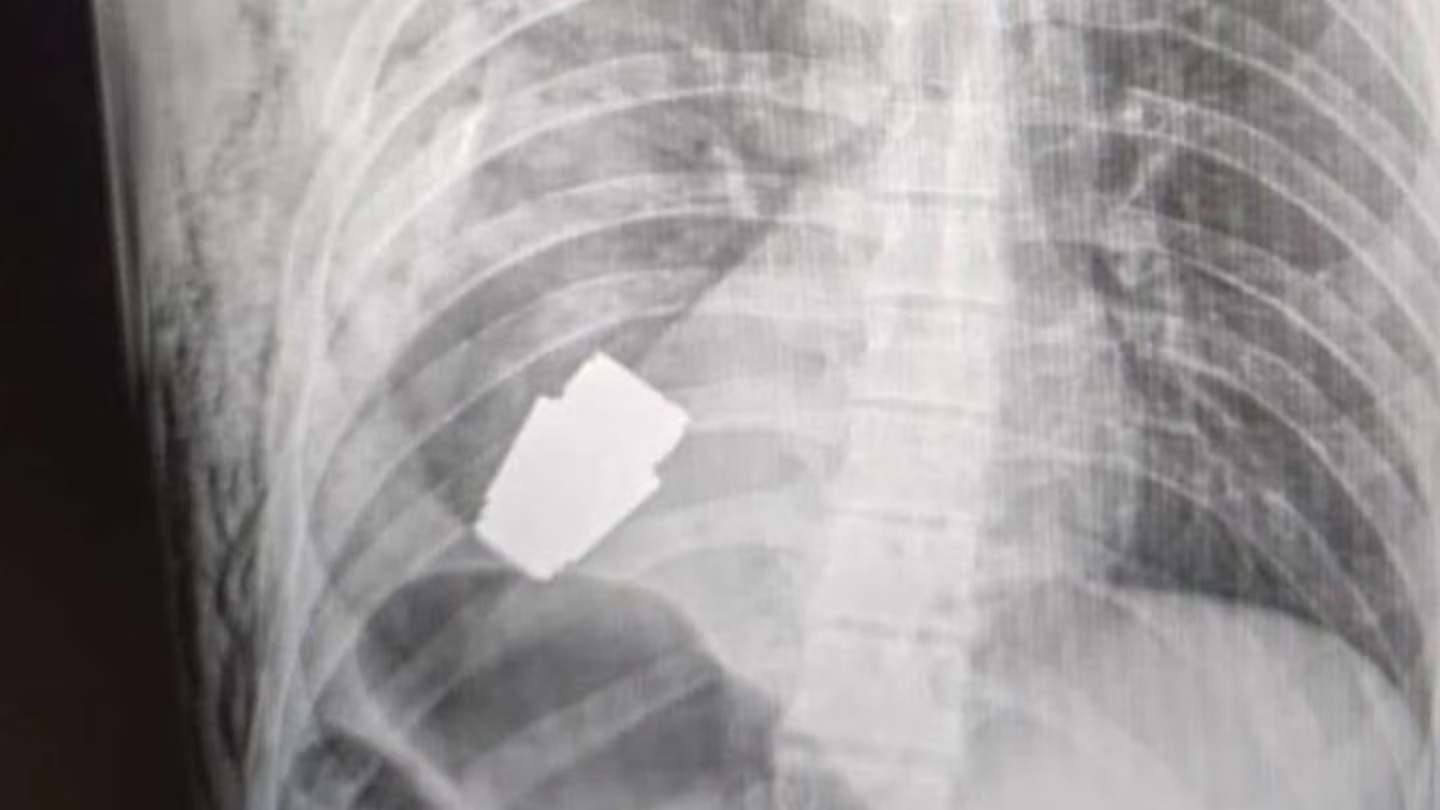

An X-ray shared on official Ukraine defence social media channels shows the explosive close to the serviceman’s heart.

Another picture shows a surgeon holding the device with just his scrubs to protect him.

Two sappers – service members who perform military engineering duties usually trained in explosives – were reportedly also in the operating theatre to ensure the safety of medical staff.

To make matters more complicated, electrocoagulation – using an electric current to control bleeding during surgery – was ruled out.

“One of the most experienced surgeons of the Armed Forces, Major General Andrew Willow, operated without electrocoagulation, as the grenade could detonate at any time,” the post said.